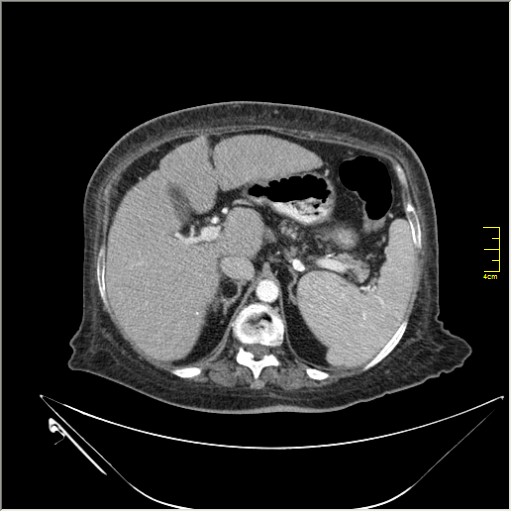

Весьма актуальная тема. Часто при проведении КТ исследования по тому или иному поводу, мы находим патологию, никак не связанную с клиникой пациента и не являющимся причиной обращения в кабинет КТ. Очень важно знать; как с этим быть, какие рекоммендации и действия необходимо предпринять. Для примера приведу одно наблюдение.

N.B. Все "находки" никак не были связаны с клиникой.

образование в правом надпочечнике

Incedentaloma правого надпочечника

Находки 2:

1.Образование правого надпочечника с плотностью жира, липома. Ничего делать не надо. По другим вариантам incidentalomas, Др. Капустин всё расписал.

2. Множество мелких конкрементов жёлчного пузыря, заполняющие до 50% просвета. С этим надо что-то делать. )))